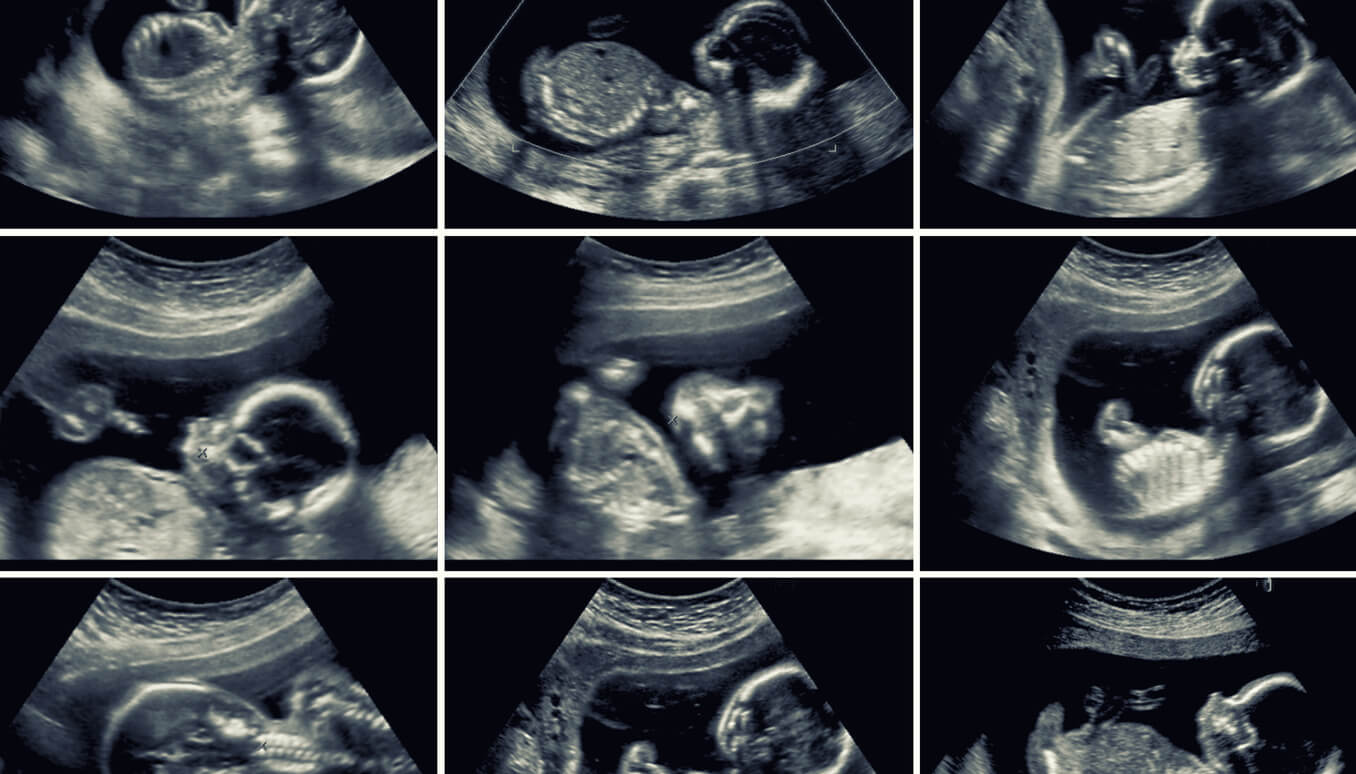

La ecografía de las 20 semanas es una prueba de rutina que permite evaluar a fondo los órganos del bebé, el útero materno y la placenta. Además de la valiosa información que ofrece, se realiza en un momento clave de la gestación.

En general, esta ecografía se realiza en 2D. Sin embargo, si el aparato lo permite, se pueden captar algunas imágenes en 3D o en 4D. Estas últimas muestran con mayor precisión los rasgos faciales del bebé e incluso, sus movimientos en tiempo real.

Es posible que el especialista combine las imágenes en 2D y 3D para lograr un análisis más completo de todas las estructuras del bebé.